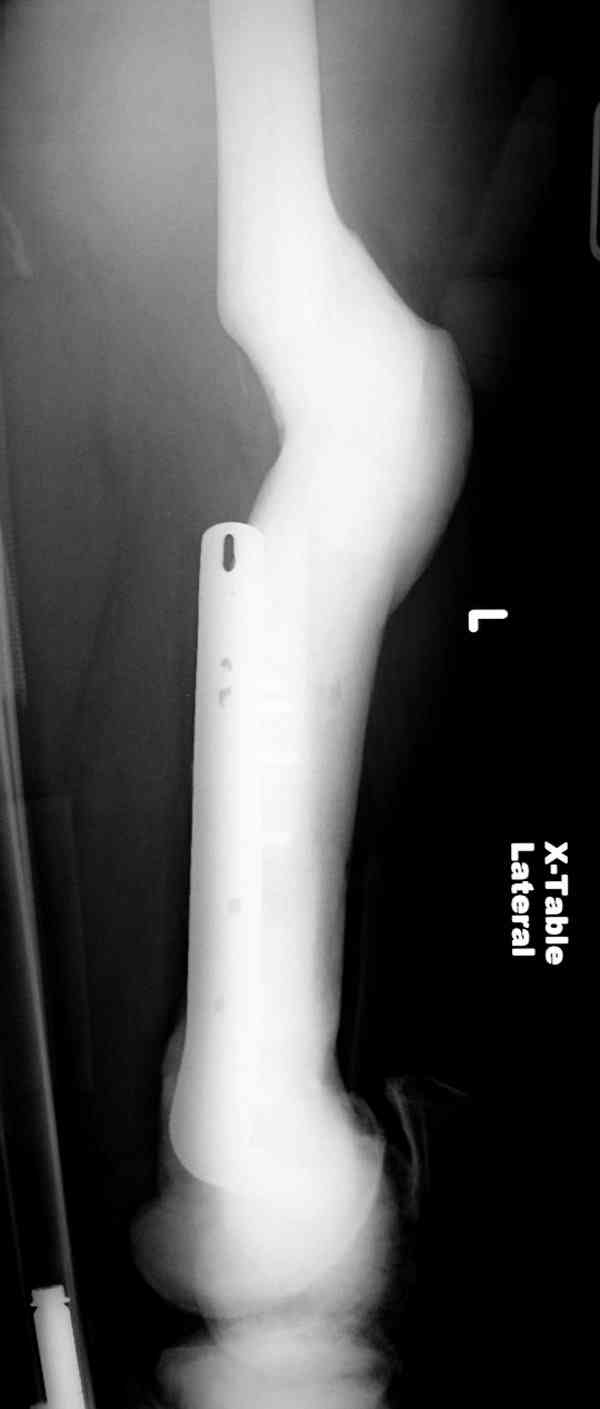

Re: [2/3] Перелом проксимального бедра

Здесь у меня дополнительные снимки с большим разрешением и в разных режимах, а то те дигитал снимки совсем очень блеклые, может, эти изображени изменят выбор тактики